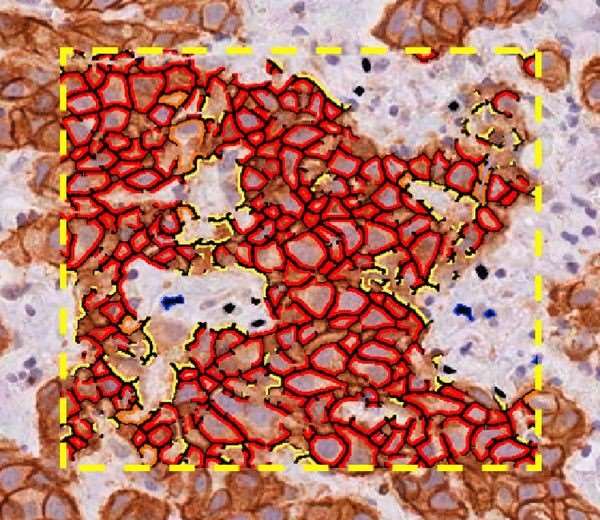

Aperio 細胞膜算法 - 快速細胞膜分析

Aperio 微血管分析算法 - 檢測和測量血管生成

Aperio 彩色解卷積算法 - 分離和量化 IHC 染色

Aperio 共定位算法 - 識別多種生物標志物相互作用